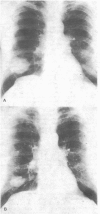

Methodichlorophen was given to 26 patients with terminal malignant disease. Eight patients received adequate doses, and five of them showed objective evidence of tumour regression while three failed to respond. Those who responded included four out of five patients with lung cancer (three with squamous-cell carcinoma and one with oat-cell carcinoma) and a patient with hypernephroma. Two patients with testicular teratomas and one with acute myeloid leukemia failed to respond. The drug may be given safely by mouth to outpatients if certain precautions are taken.